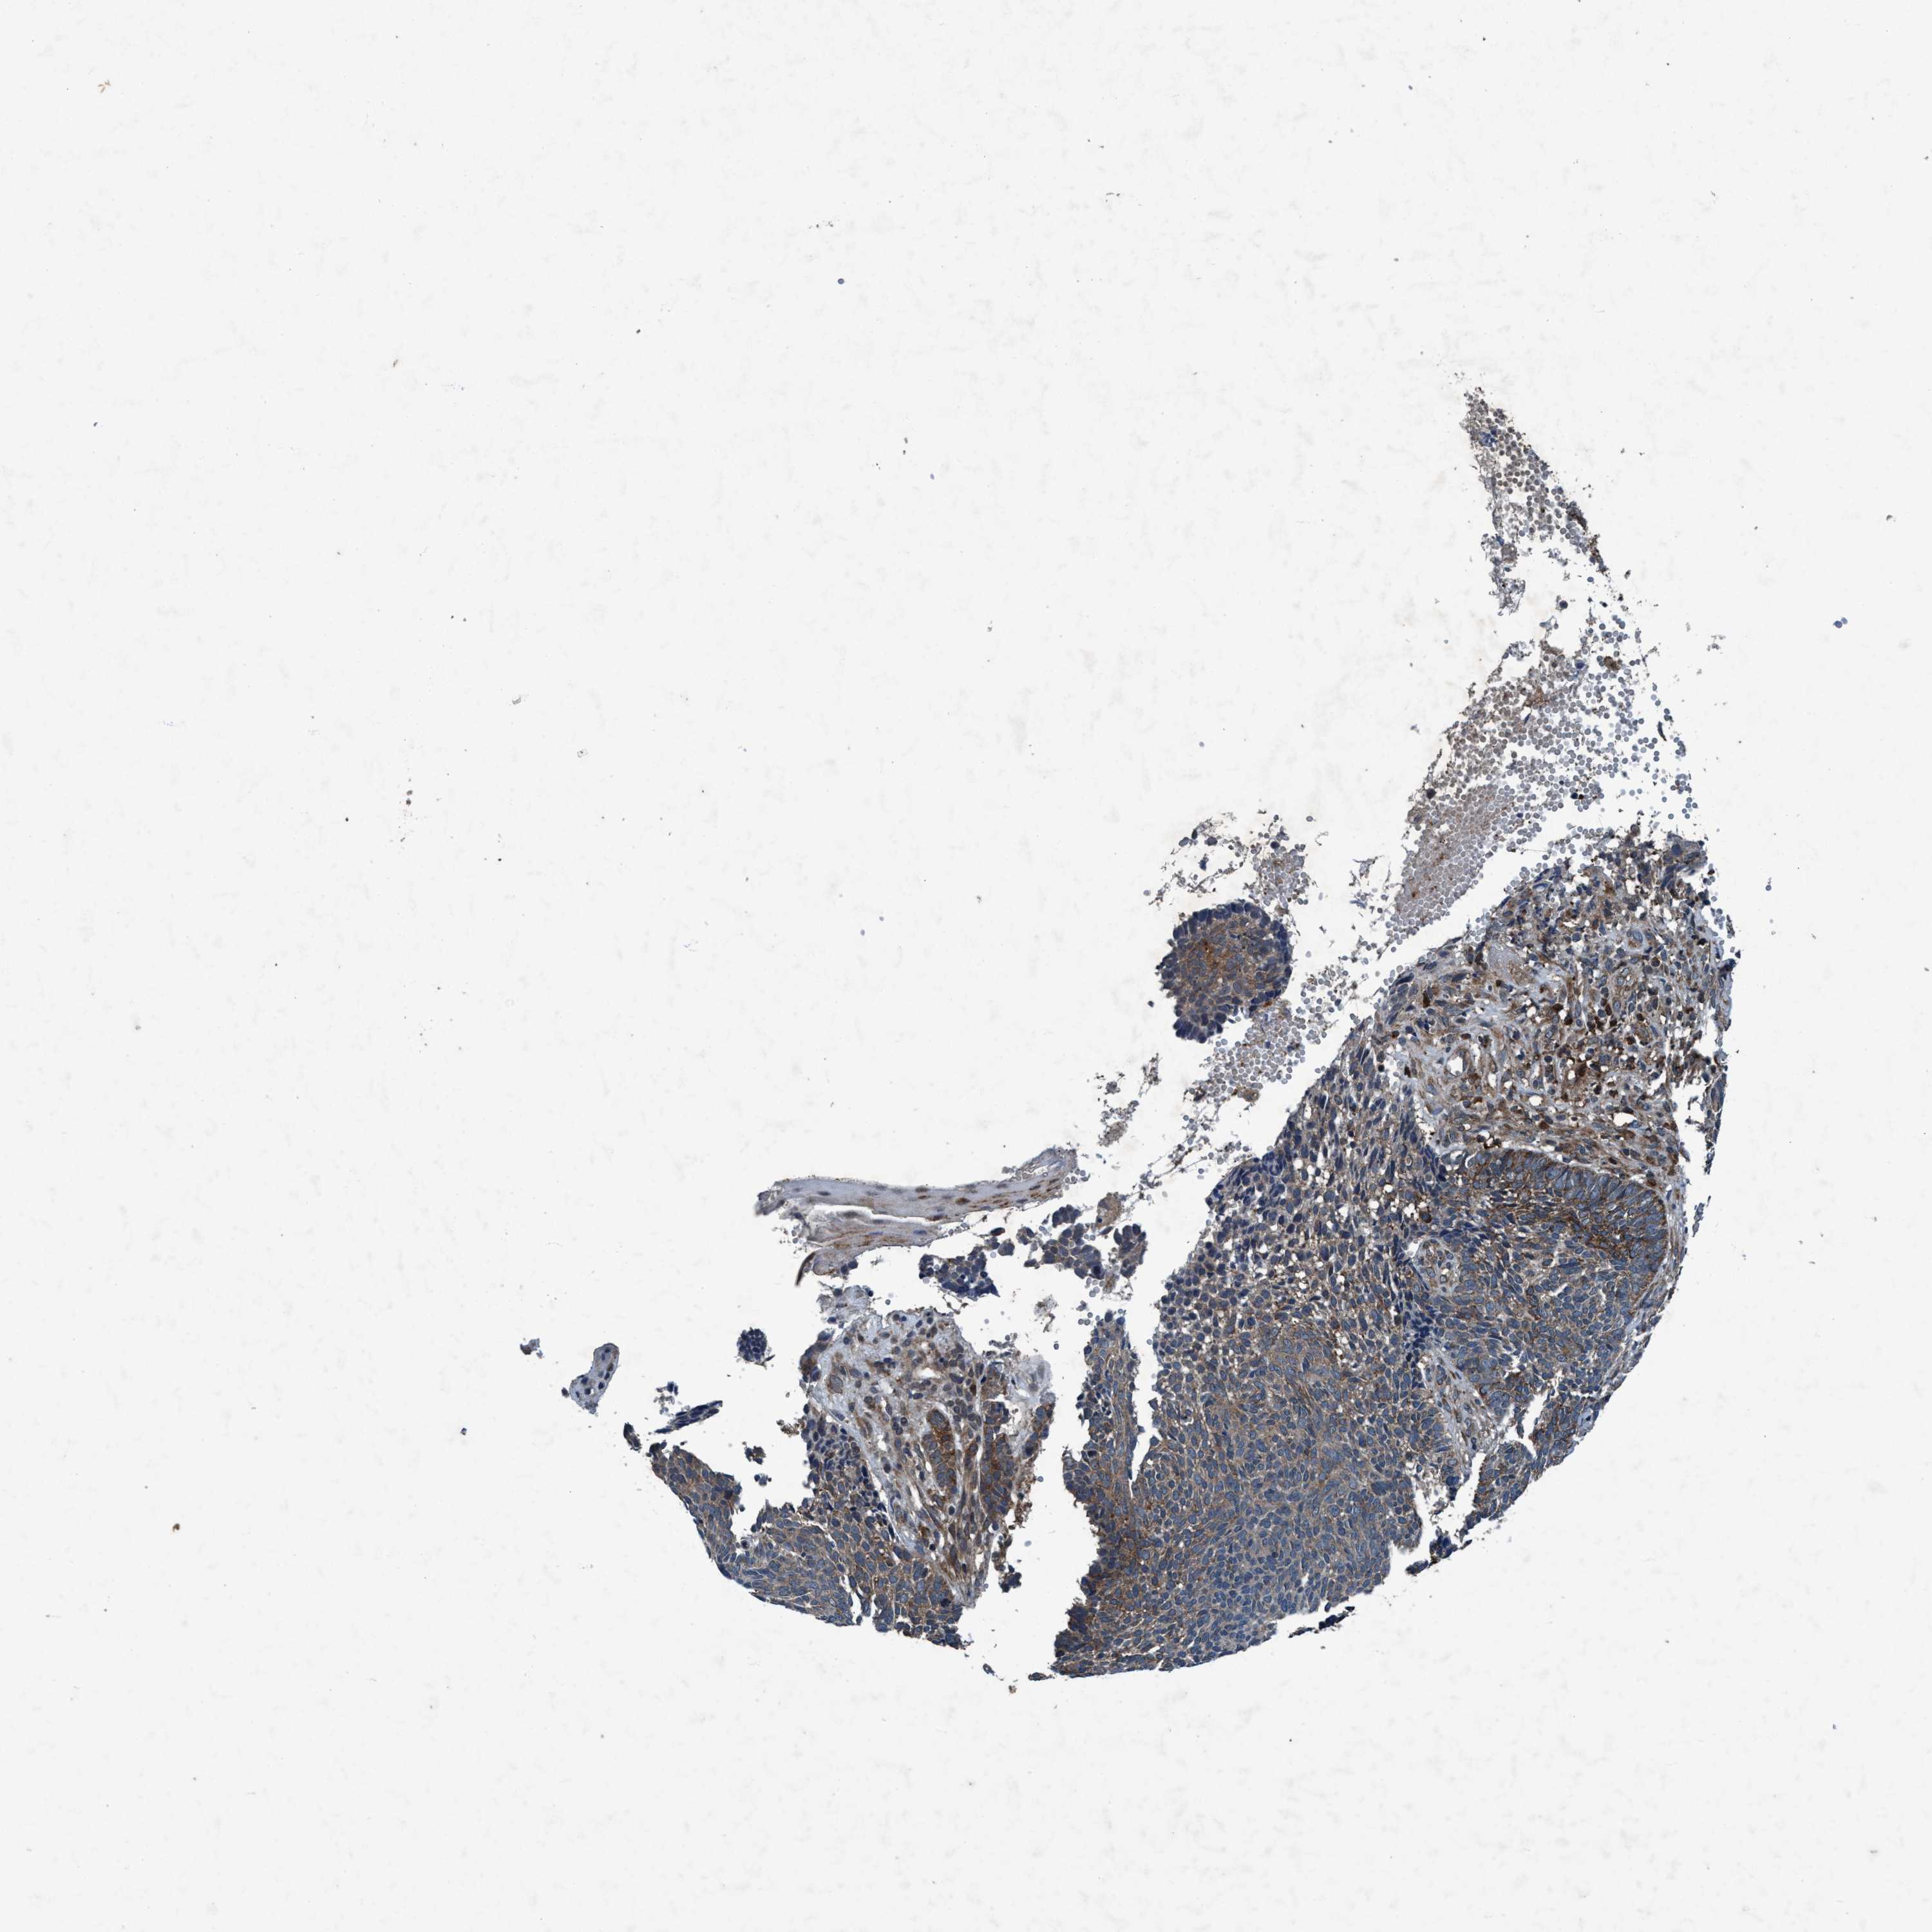

SKIN CANCER - Protein expressioni

A mouse-over function shows sample information and annotation data. Click on an image to view it in a full screen mode. Samples can be filtered based on level of antibody staining by selecting one or several of the following categories: high, medium, low and not detected. The assay and annotation is described here.

Each image is clickable and will lead to virtual microscopy that enables deeper exploration of all samples and also displays staining intensity scores, fraction scores and subcellular localization as well as patient and tissue information for each sample.

Antibody HPA064427

Antibody HPA075510

Staining

High

Medium

Low

Not detected

Intensity

Strong

Moderate

Weak

Negative

Quantity

>75%

75%-25%

<25%

None

Location

Nuclear

Cytoplasmic/membranous

Cytoplasmic/membranous,nuclear

Basal cell carcinoma

BCC, high aggressive

Squamous cell carcinoma, NOS